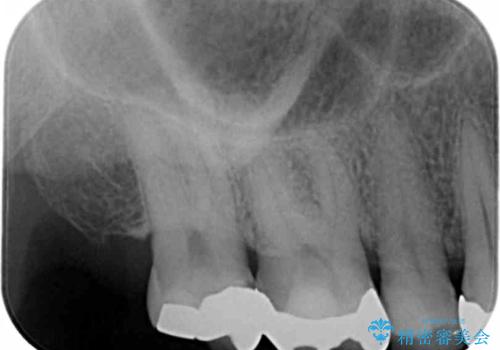

- フロスをしたときにひっかかりのある銀歯の修復を希望され来院されました。

銀歯の下には虫歯の再発が見られましたが、丁寧に除去を行いゴールドインレーによる修復を行いました。